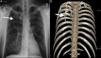

A) Radiografía posteroanterior de tórax, que muestra una densidad lineal vertical en el lado derecho, con un grado de opacidad similar al del hueso, que se extiende en sentido inferomedial desde el centro del tórax. B) La técnica de representación volumétrica con reconstrucción en 3D muestra claramente la presencia de una costilla supernumeraria originada a partir de la costilla proximal y extendida en sentido inferomedial.

La costilla intratorácica (CI) es una anomalía congénita muy rara, que resulta de la fusión incompleta de los esclerotomos adyacentes1. La literatura describe 3 tipos: los tipos 1A y 1B definen las costillas supernumerarias que se originan a partir del cuerpo vertebral o la costilla proximal, respectivamente, el tipo 2 incluye las costillas bífidas originadas a partir de la costilla distal, y el tipo 3 corresponde a las costillas que se deprimen hacia la cavidad torácica2. Las CI de tipo 1A, costillas accesorias originadas a partir del cuerpo vertebral, en general descienden en sentido vertical. El curso vertical del tipo 1A se asocia a un colapso permanente del lóbulo inferior y puede confundirse con una masa mediastínica o paravertebral2. Un varón de mediana edad acudió a nuestro hospital por presentar tos y escalofríos. La radiografía de tórax (proyección posteroanterior) mostró una densidad lineal vertical en el lado derecho, que se extendía en sentido inferomedial desde el centro del tórax (fig. 1A). En la tomografía computarizada se observó una costilla intratorácica que se originaba en la parte inferomedial de la tercera costilla; la técnica de representación volumétrica (volume rendering) con reconstrucción en 3D mostró, en mayor detalle, la envergadura de la costilla supernumeraria, una CI de tipo 1B (fig. 1B). A pesar de que en la literatura se ha sugerido que la tomografía computarizada es el método que permite clasificar mejor una CI1, consideramos que en la era de la radiología digital este tipo de estudio de imagen es redundante, excepto para el tipo 1A.